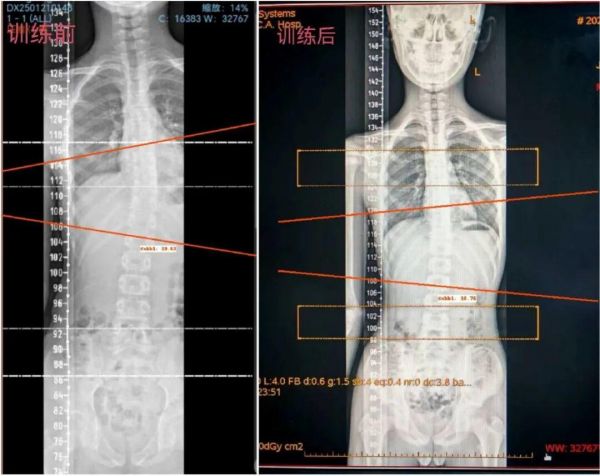

本次冬令營以德國施羅斯療法(Schroth Method)為核心,其核心理念是三維自我矯正。系統(tǒng)性矯正脊柱在冠狀面(側(cè)彎)、矢狀面(生理曲度異常)和水平面(旋轉(zhuǎn))的畸形。

1.核心療法:以德國施羅斯療法為主,通過呼吸訓(xùn)練、肌力平衡調(diào)整、三維矯正側(cè)彎與旋轉(zhuǎn)等方式。

1. 攜帶近期脊柱全長X光片